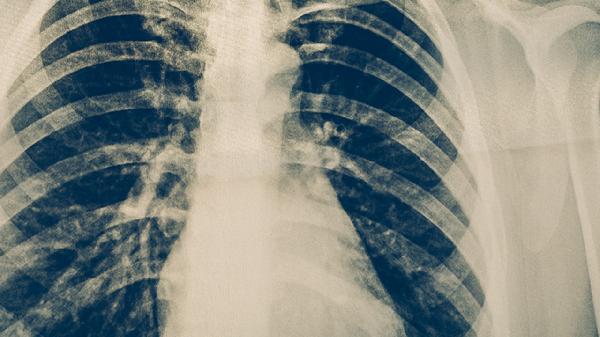

治療期間每月需復(fù)查痰涂片、胸部X線,評估治療效果。完成療程后每3-6個月隨訪1次,持續(xù)2年。復(fù)查項目包括痰菌檢查、肝功能檢測等,以及時發(fā)現(xiàn)復(fù)發(fā)或藥物不良反應(yīng)。若出現(xiàn)咳嗽加重、體重下降等癥狀需提前就診。